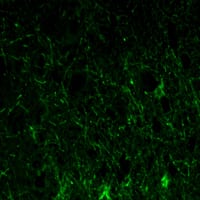

Immunofluorescence analysis of paraffin-embedded human lobe of brain tissues using GFAP mouse mAb (green).